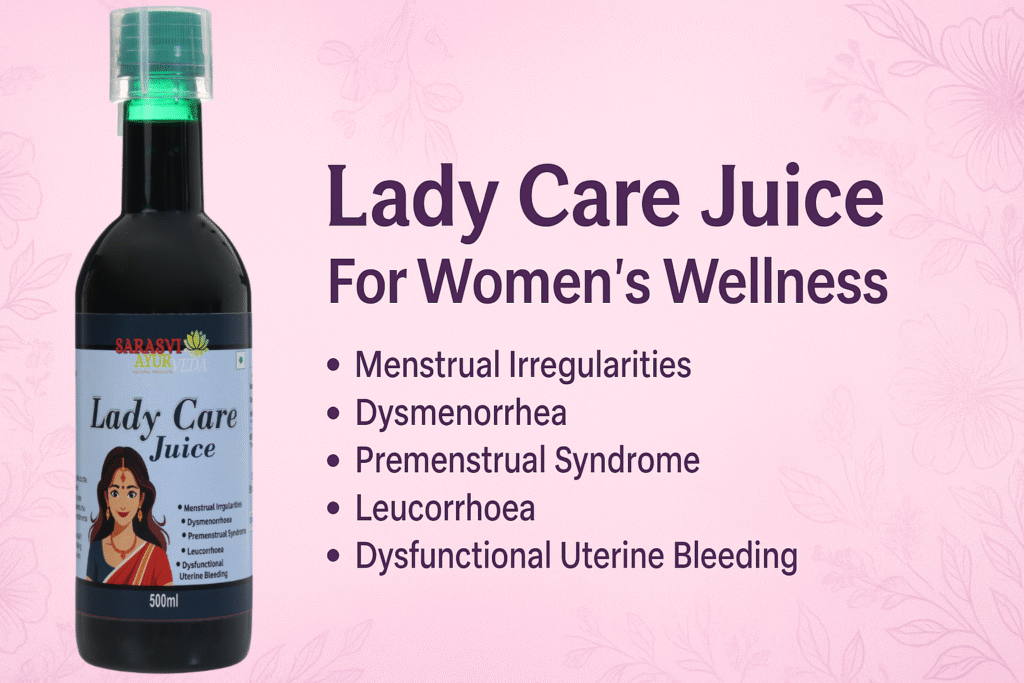

What is Lady Care Juice?